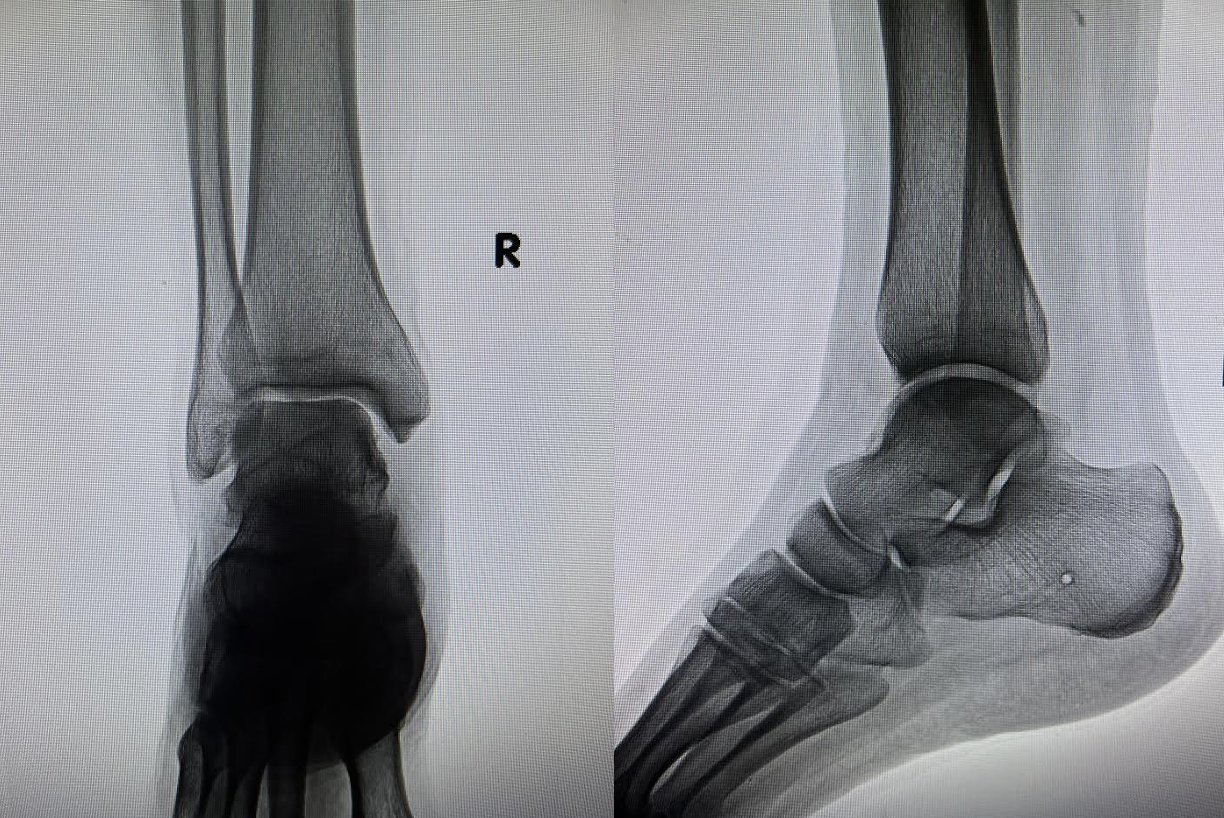

A 50-year-old male with type 2 diabetes and chronic joint pain presented to our clinic after several previous emergency department visits with leg pain and swelling. An ultrasound had ruled out deep vein thrombosis and X-ray imaging ruled out acute fractures (see first images to left). The patient denied any known trauma or injury to the area.

Physical examination showed pain with active and passive range of motion about the ankle most significant with inversion and dorsiflexion, as well as pain on palpation of the anterior medial ankle. Multiplanar, multisequence MR images of the right ankle without gadolinium contrast showed extensive marrow edema in the talus and sinus tarsi, as well as osteochondral cystic changes with bony irregularity involving the medial talar dome and focal cartilage defect to the anterior midline tibial plafond (see MRI images to left).